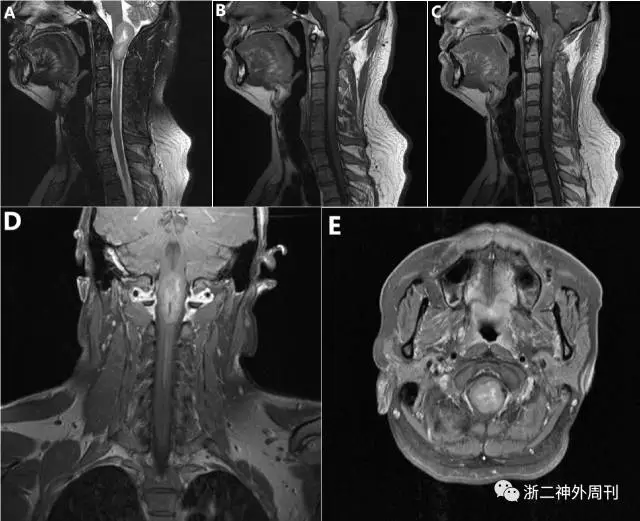

入院后查颈椎增强MRI(图1)提示枕骨大孔区髓内肿块,大小约23.0mmx22.3mmx42.3mm(左右x前后x上下)。T1以等信号为主,T2以稍高信号为主,内见不规则裂隙状坏死区;增强后坏死周围呈花环样强化,外围中等强化,肿块下方脊髓中央管局段性扩张,生物学行为偏良性肿瘤考虑。

图1. 术前MRI,枕骨大孔区髓内肿块,大小约23.0mmx22.3mmx42.3mm(左右x前后x上下)。T1以等信号为主(图B),T2以稍高信号为主(图A),内见不规则裂隙状坏死区;增强后(图C-E)坏死周围呈花环样强化,外围中等强化,肿块下方脊髓中央管局段性扩张。